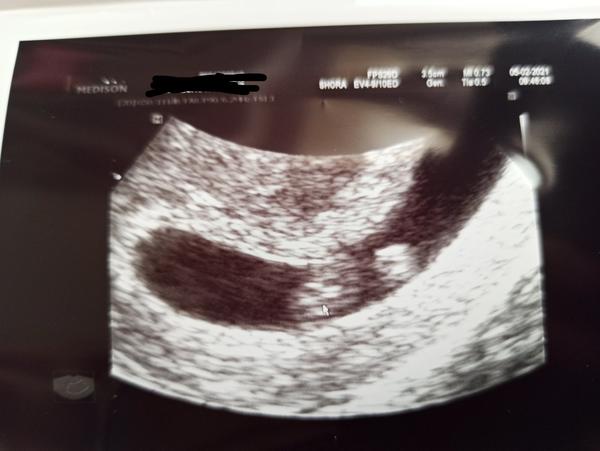

Tady jsou fotky 🙂